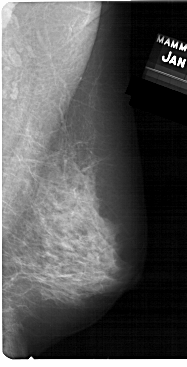

A_1130_1.LEFT_CC

LEFT_CC LINES 5071 PIXELS_PER_LINE 2311 BITS_PER_PIXEL 12 RESOLUTION 43.5 OVERLAY